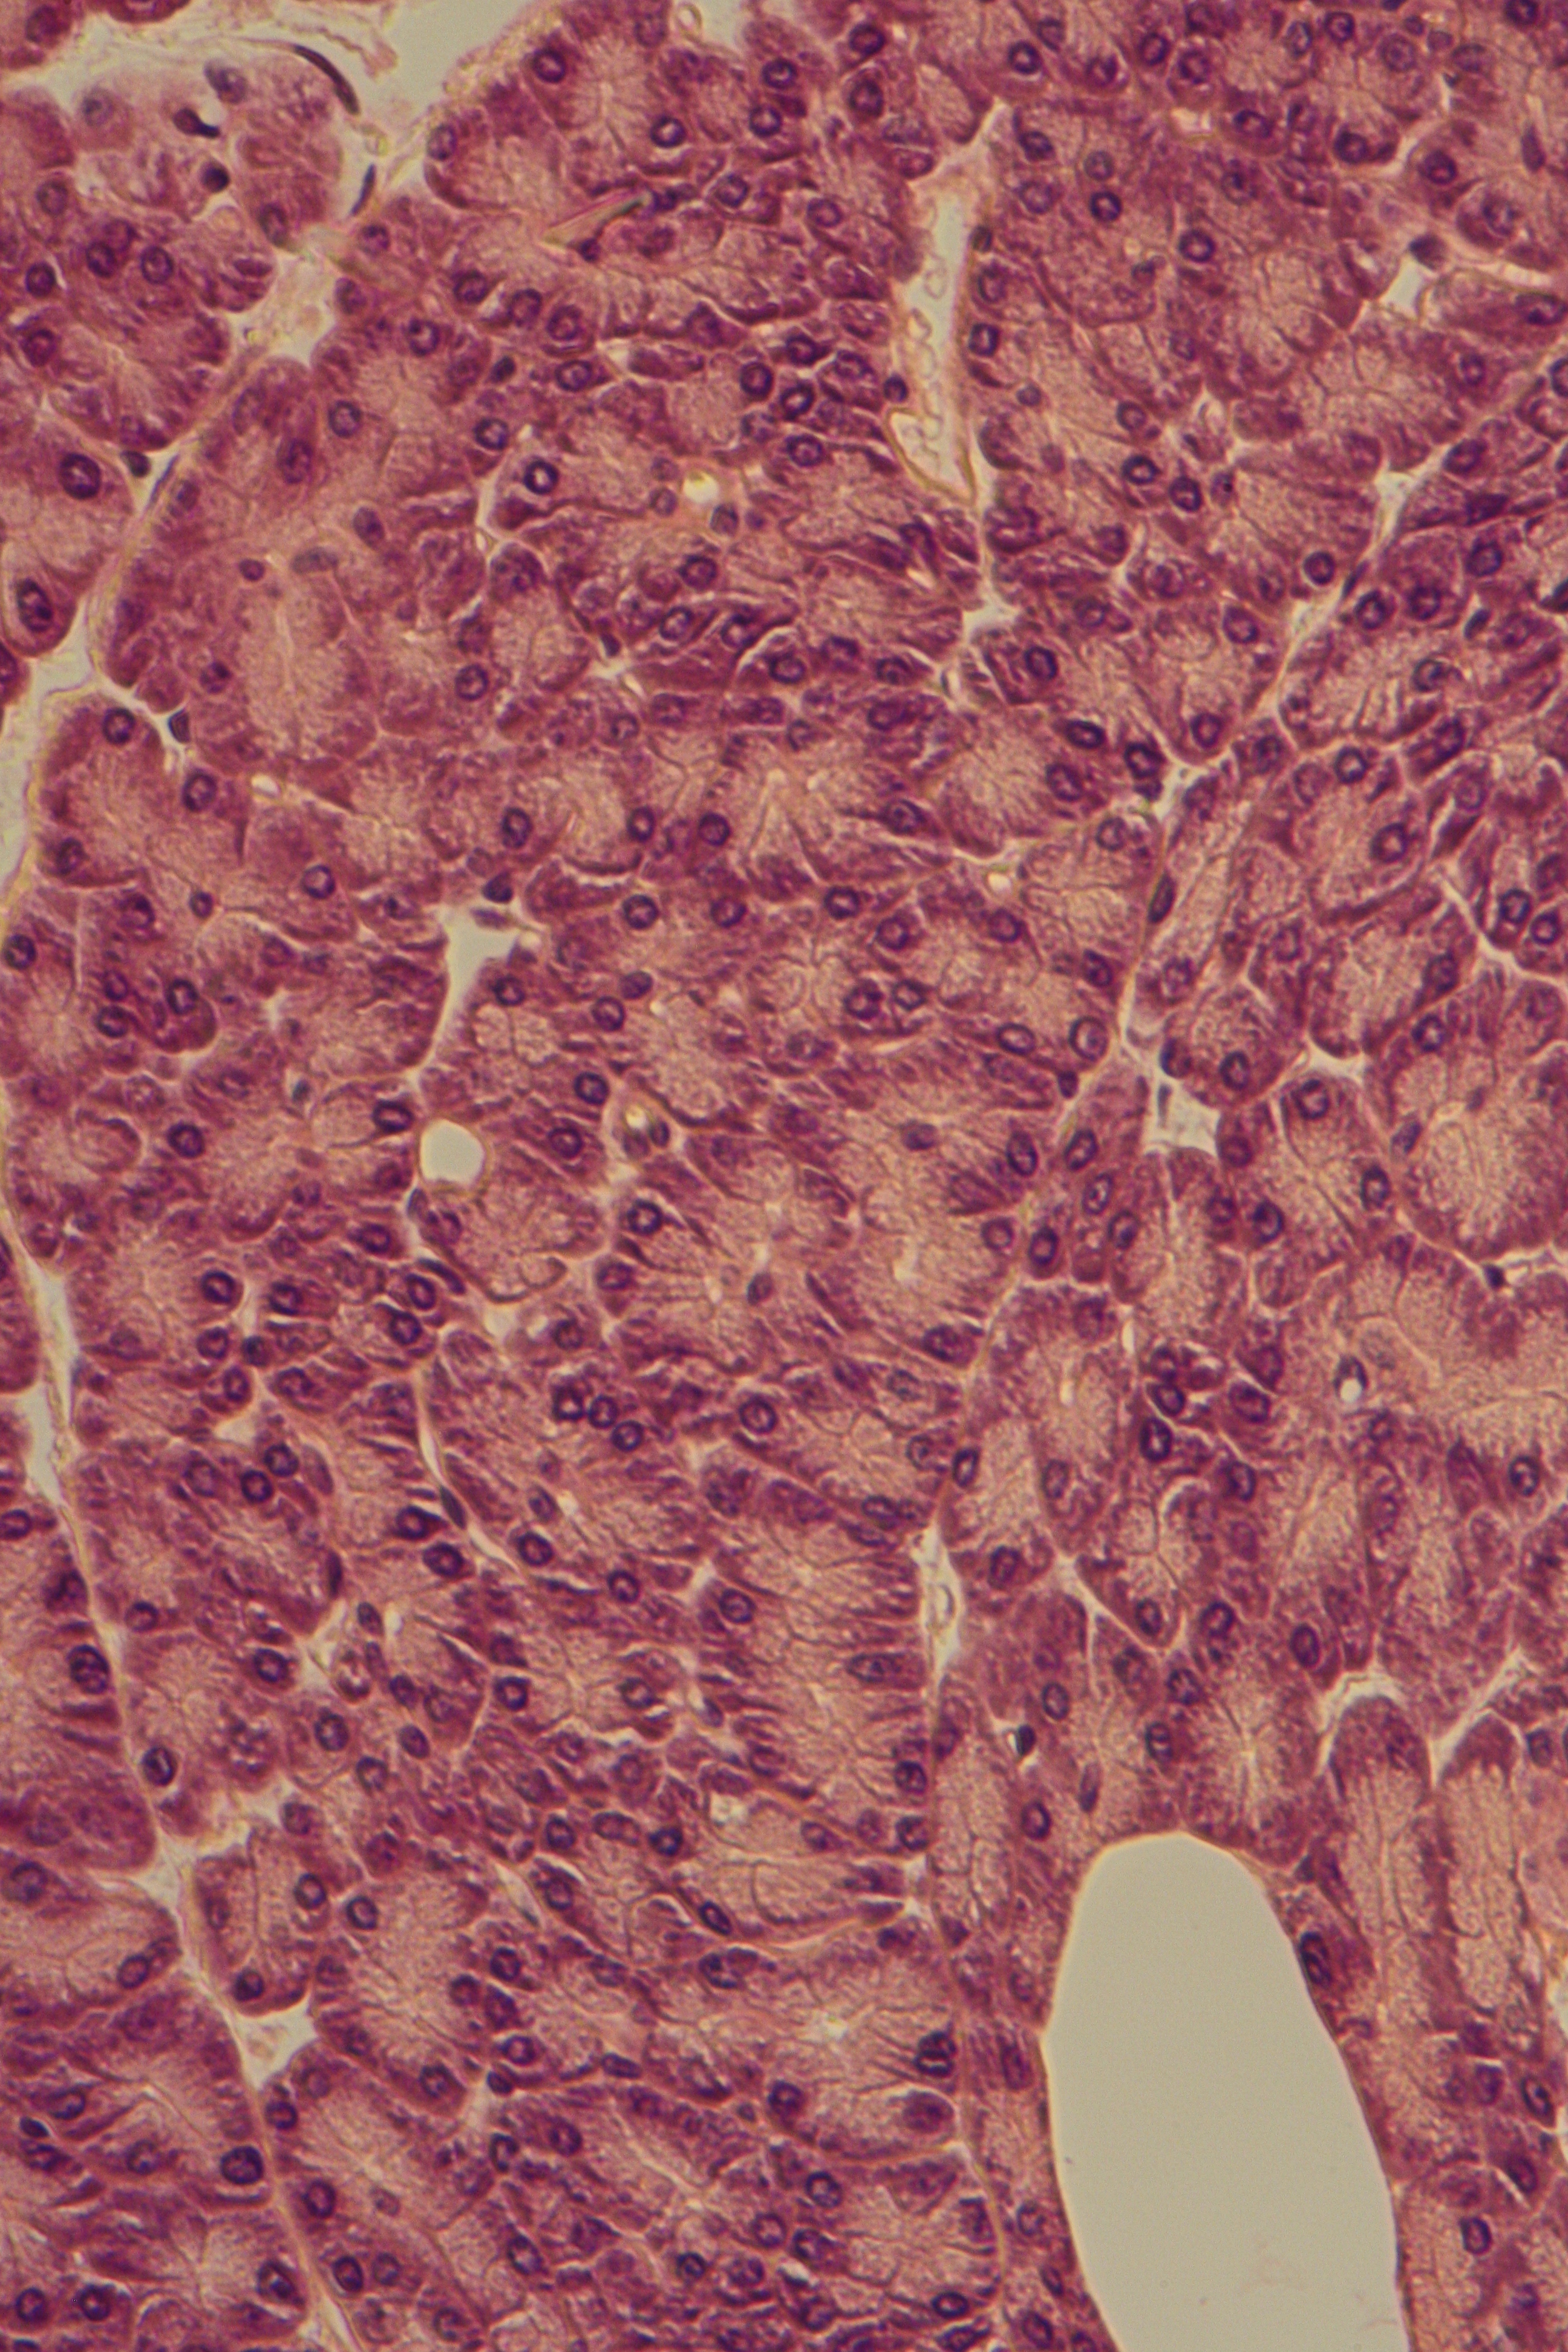

Pancreas with exocytic vesicles